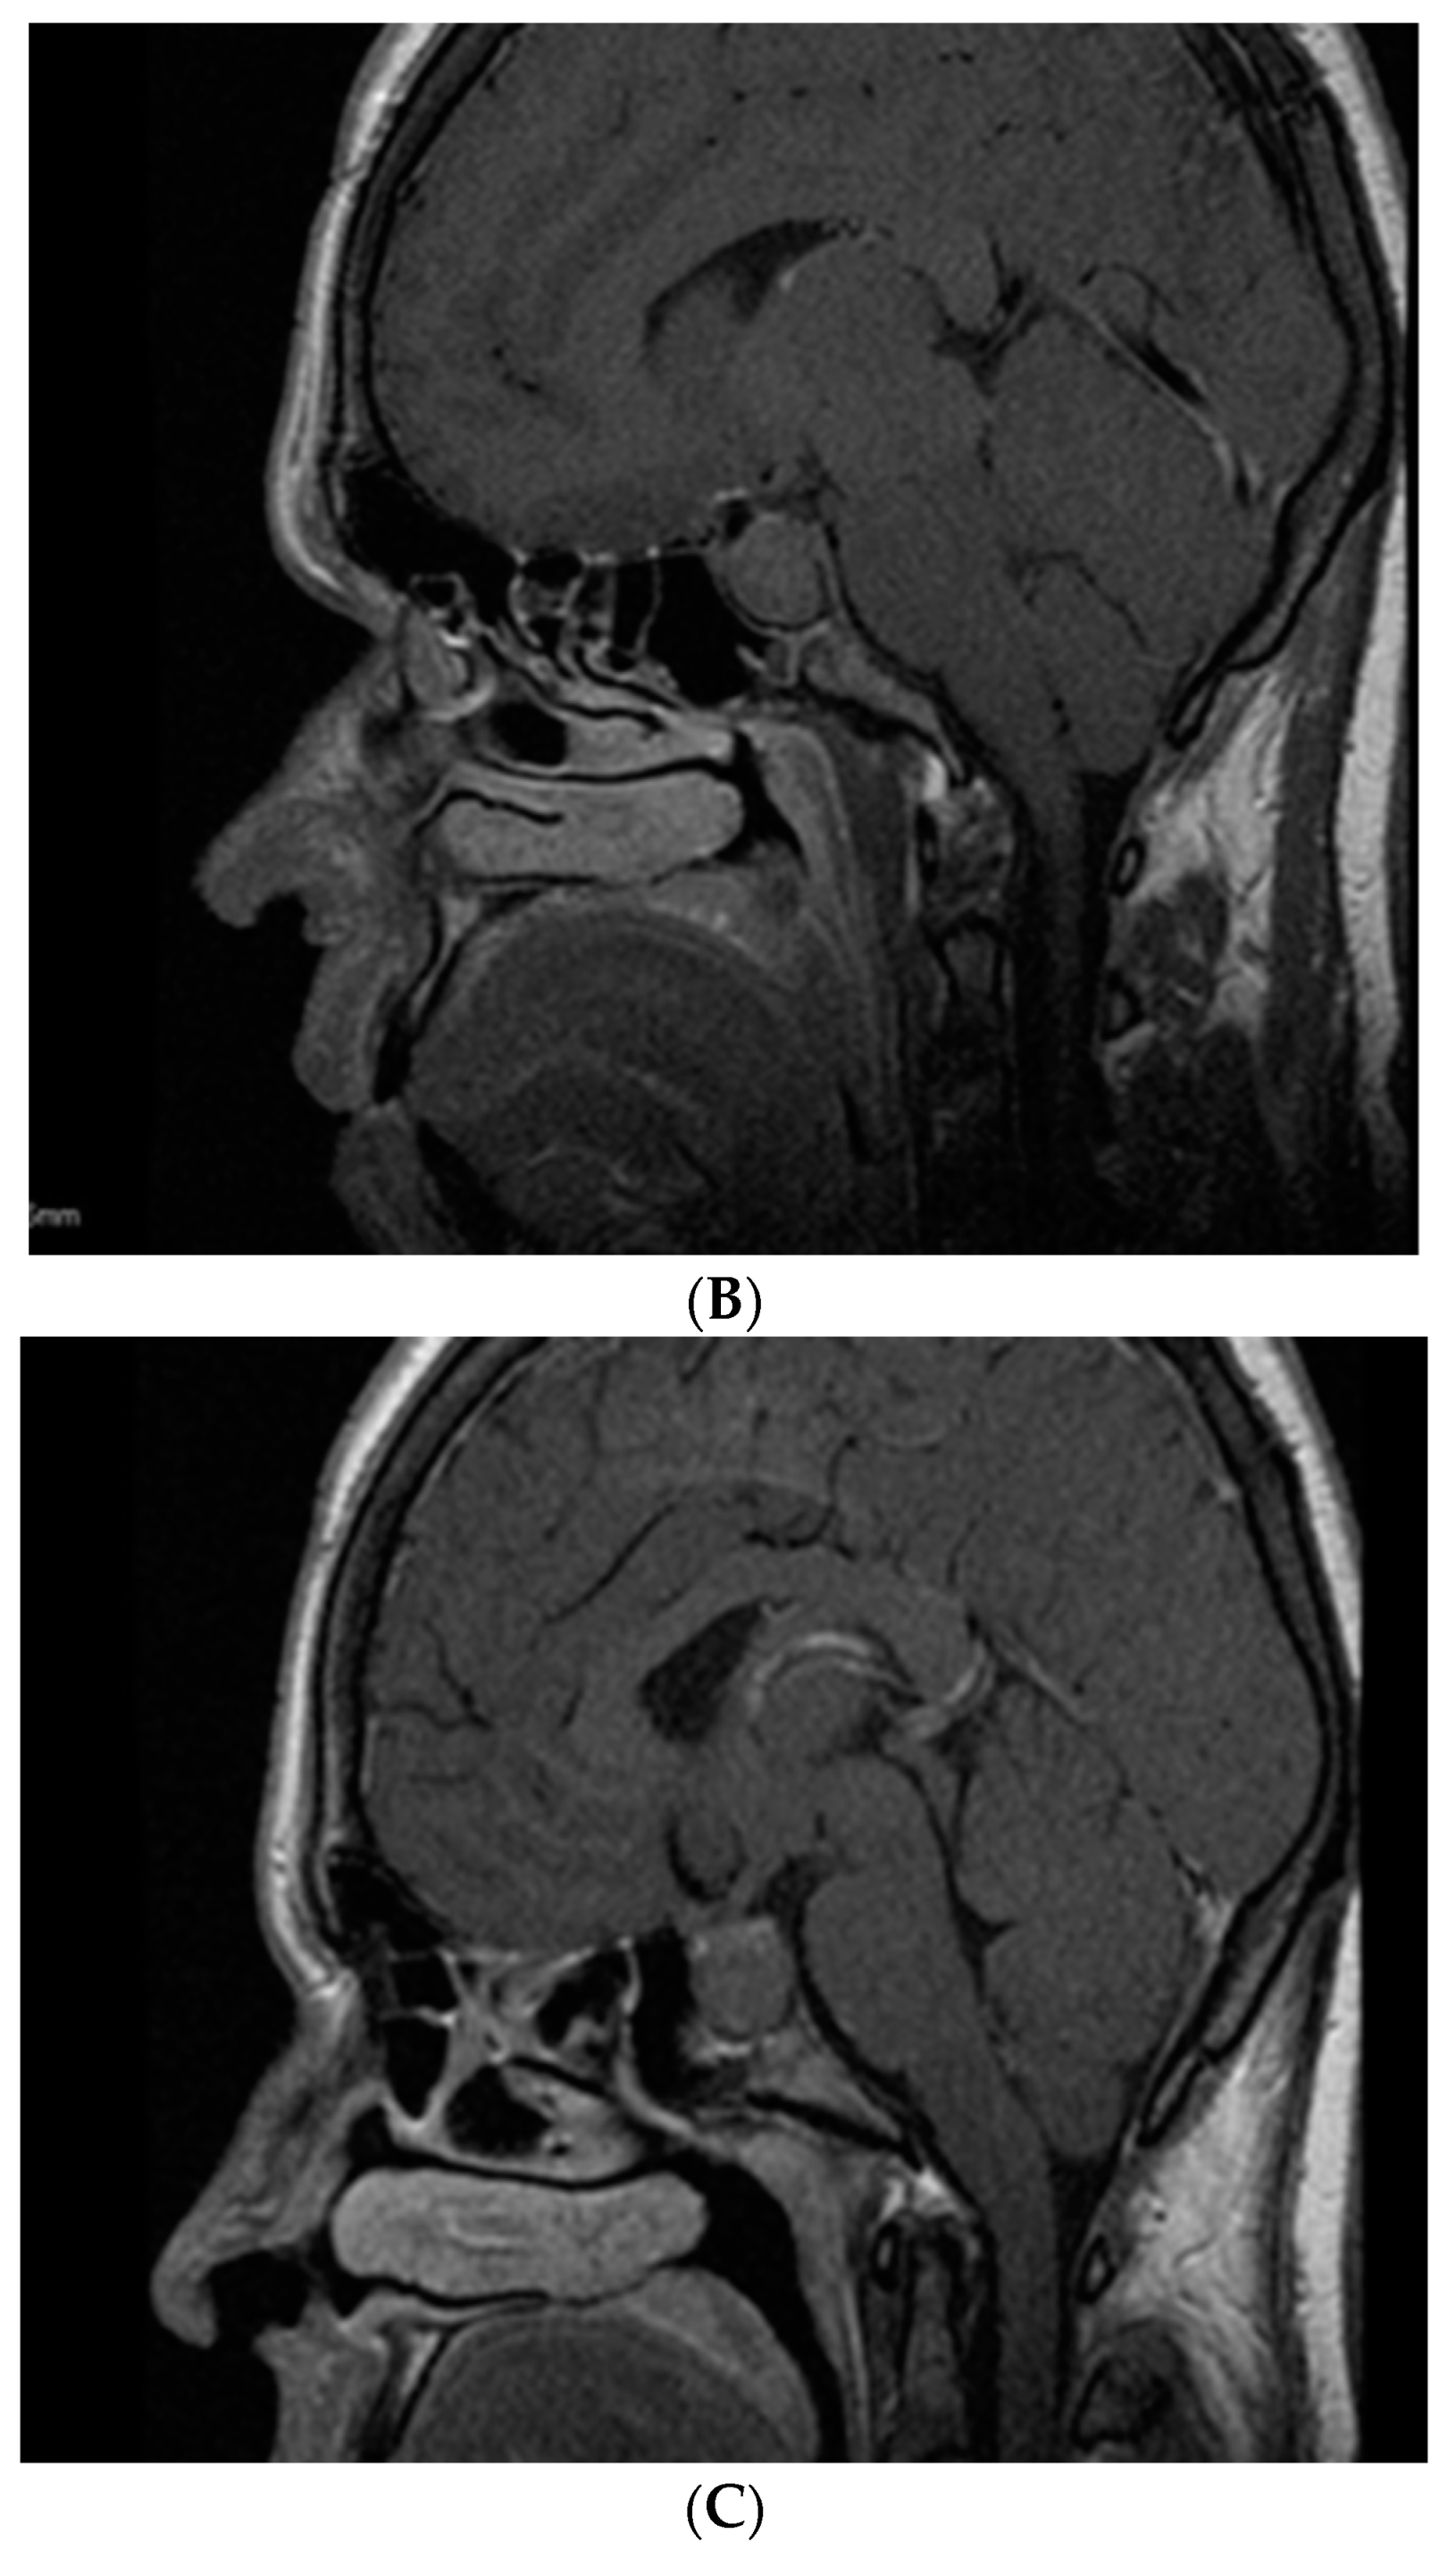

- Kasuki, L.; Neto, L.V.; Takiya, C.M.; Gadelha, M.R. Growth of an aggressive tumor during pregnancy in an acromegalic patient. Endocr. J. 2012, 59, 313–319. [Google Scholar] [CrossRef] [PubMed]

- Hannon, A.M.; Frizelle, I.; Kaar, G.; Hunter, S.J.; Sherlock, M.; Thompson, C.J.; O’Halloran, D.J.; Irish Pituitary Database Group. Octreotide use for rescue of vision in a pregnant patient with acromegaly. Endocrinol. Diabetes Metab. Case Rep. 2019, 2019, 19-0019. [Google Scholar] [CrossRef] [PubMed]

- Dicuonzo, F.; Purciariello, S.; De Marco, A.; Guastamacchia, E.; Triggiani, V. Inoperable Giant Growth Hormone-secreting Pituitary Adenoma: Radiological Aspects, Clinical Management and Pregnancy Outcome. Endocr. Metab. Immune Disord. Drug Targets 2019, 19, 214–220. [Google Scholar] [CrossRef]